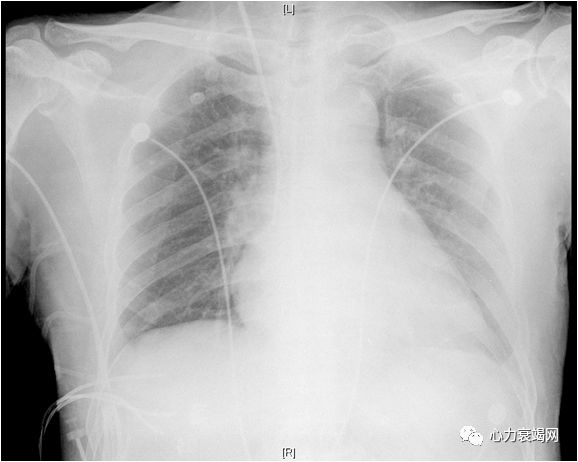

心脏扩大

心尖部室壁瘤

心律失常

心房颤动

心房扑动

心功能III级